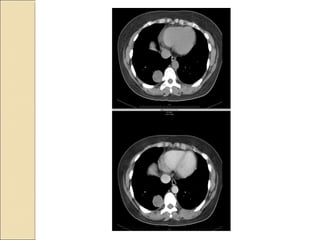

A resident in radiology presents two interesting cases: the first involves a harmatoma, and the second concerns a patient with double superior vena cava and tracheal bronchus. Both cases provide learning opportunities for radiology residents to recognize rare anatomical variations and abnormalities.